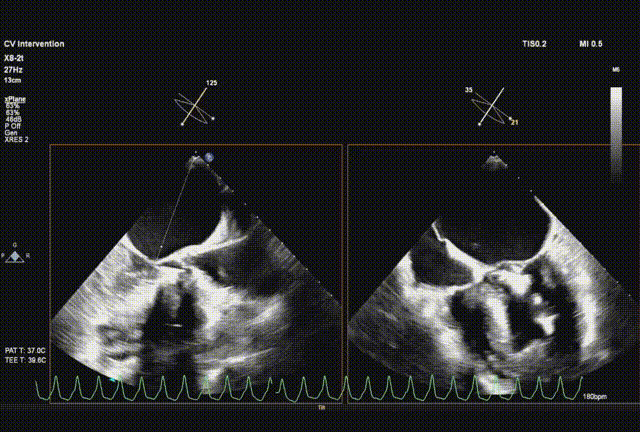

超声引导直头导丝跨瓣成功

交换送入猪尾导管并确认到达心尖

采样线扫到左室心尖并送入safari导丝

球囊预扩

输送系统顺利跨瓣

瓣膜初始释放到喇叭状形态并定位植入深度

采样线扫到无窦,180起搏,长轴视图下快速释放到工作位

超声从左至右,最后无冠窦侧评估深度合适

起搏下完全释放瓣膜

左右旋转系统并前送,观察无瓣膜移动,回撤导丝后再撤出系统

术后超声评估,未见瓣周漏,平均跨瓣压15 mmHg,血流速度197 cm/s